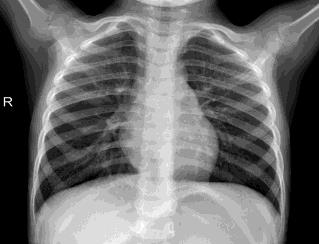

Pneumonia, a respiratory infection brought on by bacteria or viruses, affects a large number of people, especially in developing and impoverished countries where high levels of pollution, unclean living conditions, and overcrowding are frequently observed, along with insufficient medical infrastructure. Pleural effusion, a condition in which fluids fill the lung and complicate breathing, is brought on by pneumonia. Early detection of pneumonia is essential for ensuring curative care and boosting survival rates. The approach most usually used to diagnose pneumonia is chest X-ray imaging. The purpose of this work is to develop a method for the automatic diagnosis of bacterial and viral pneumonia in digital x-ray pictures. This article first presents the authors' technique, and then gives a comprehensive report on recent developments in the field of reliable diagnosis of pneumonia. In this study, here tuned a state-of-the-art deep convolutional neural network to classify plant diseases based on images and tested its performance. Deep learning architecture is compared empirically. VGG19, ResNet with 152v2, Resnext101, Seresnet152, Mobilenettv2, and DenseNet with 201 layers are among the architectures tested. Experiment data consists of two groups, sick and healthy X-ray pictures. To take appropriate action against plant diseases as soon as possible, rapid disease identification models are preferred. DenseNet201 has shown no overfitting or performance degradation in our experiments, and its accuracy tends to increase as the number of epochs increases. Further, DenseNet201 achieves state-of-the-art performance with a significantly a smaller number of parameters and within a reasonable computing time. This architecture outperforms the competition in terms of testing accuracy, scoring 95%. Each architecture was trained using Keras, using Theano as the backend.